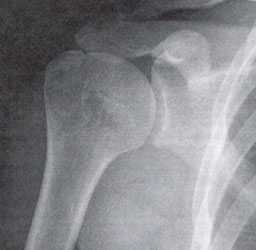

Импинджмент-синдром.а. МРТ плечевого сустава, б. рентгенография плечевого сустава.

Для верификации диагноза используют также тест с введением лидокаина (с стероидами) в суставную сумку. Это вызывает временное уменьшение интенсивности боли.